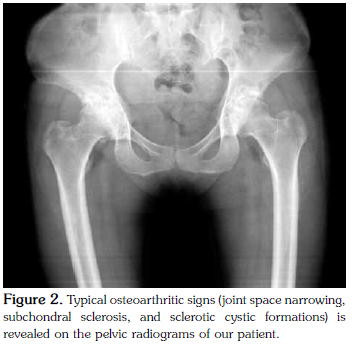

A physical examination revealed decreased ROM in both wrists and the MCP joints with accompanying flexion deformities; however, the affected joints did not demonstrate any signs of active inflammation. Furthermore, the patient's hip joint movements were painful and restricted. Typical signs of osteoarthritis (OA) (irregular narrowing of joint spaces, subchondral sclerosis, and sclerotic cyst formation) were seen on hand radiograms (Figure 1). Strikingly, the distal interphalangeal (DIP) and PIP joints were intact, and hook-like osteophytic formations on the heads of the metacarpal bones were seen, which is typical of hemochromatosis. Pelvic radiograms revealed irregular joint space narrowing, sclerotic changes, and subchondral cysts involving the hip joints (Figure 2). Additionally, the laboratory findings showed a normal erythrocyte sedimentation rate (ESR) and C-reactive protein (CRP) levels, and the patient tested negative for rheumatoid factor (RF) as well as anti-cyclic citrullinated peptide (anti-CCP) and antinuclear antibodies (ANA). Furthermore, the serum uric acid level was normal, and the liver function test results were within normal limits. Although the serum iron and ferritin levels were also within normal limits, the transferrin saturation rate was higher (69.71%) than normal (<55%). Moreover, the patient's estimated hepatic iron concentration was 44±20 μmol/g (normal <36 μmol/g) using T2 sequences in abdominal magnetic resonance imaging (MRI). A genetic examination also determined the existence of a homozygous H63D mutation; therefore, the patient was diagnosed with HH based on the clinical, radiological, and laboratory findings.